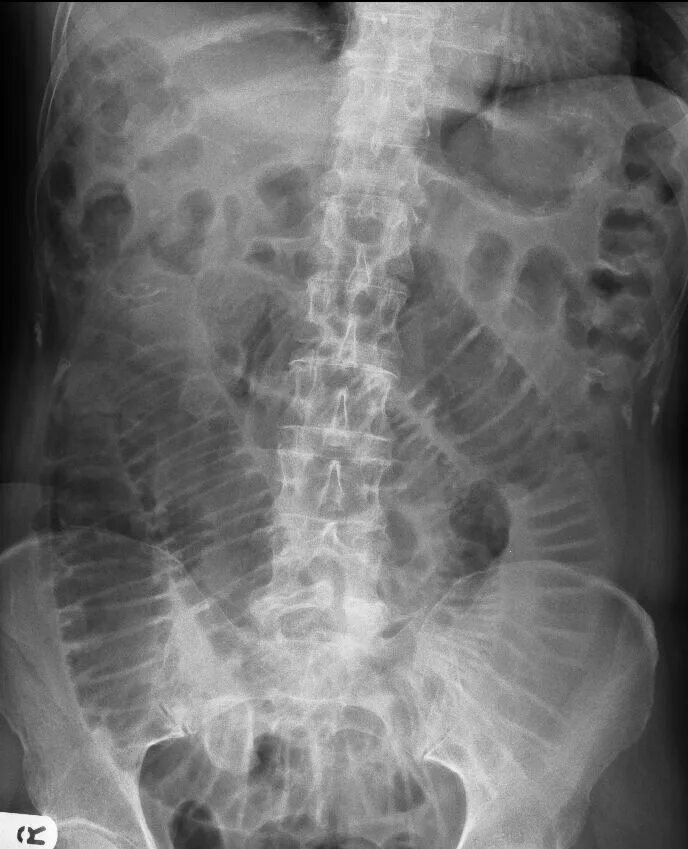

Симптом чаши